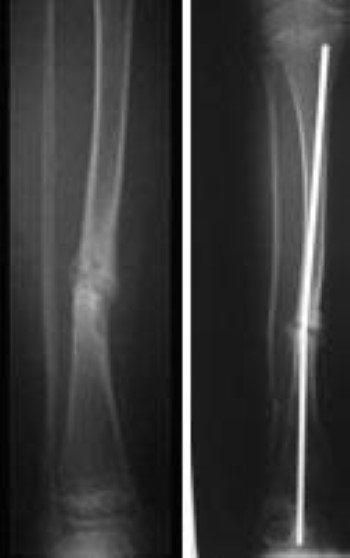

Pseudoarthrosis Before and After Surgery

(Left, left center) Pre-operative radiographs showing two different views of pseudoarthrosis in a 2-year-old girl. (Right center, right) Radiographs taken at 2-year follow-up after treatment with flexible intramedullary titanium nails.

Reproduced with permission from Vander Have K, Hensinger, R, Caird M, Johnston C, Farley F: Congenital Pseudoarthrosis of the Tibia. J Am Acad Orthop Surg 2008; 16(4): 228-236.

Pseudoarthrosis of the tibia

(Left): An X-ray of a pseudarthrosis of the tibia in a 5-year-old child. (Right): The fracture is held together with a rod inside the bone.

Reproduced with permission from Lewis TR: Congenital pseudarthrosis of the tibia. Orthopaedic Knowledge Online Journal 2012. Accessed Apr 22, 2013.